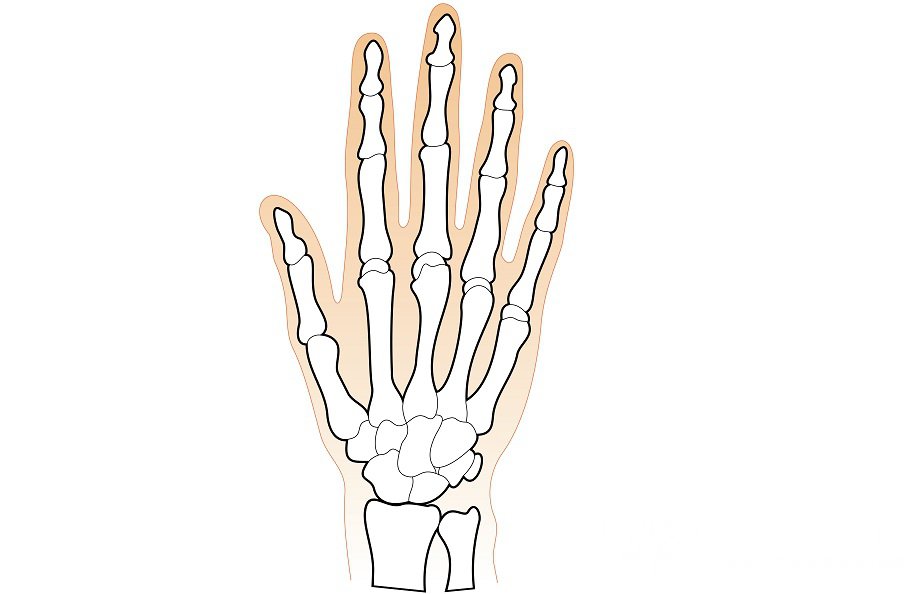

Кости запястья

Кости запястья. Общая информация

Кости запястья образует совокупность из 8 маленьких губчатых костей, которые располагаются в два ряда, в каждом из которых находится по 4 косточки.

Первый или проксимальный ряд, расположенный ближе к предплечью, состоит из следующих костей, представленных по порядку, начиная с большого пальца:

- ладьевидной или os scaphoideum;

- полулунной или os lunatum;

- трехгранной или os triquetrum;

- гороховидной или os pisiforme.

Соединение первых трех косточек образует эллиптическую суставную поверхность, которая сочленяет запястье и дистальный конец лучевой кости. Гороховидная кость запястья, которую принято относить к сесамовидной косточке, в свою очередь, присоединена к трехгранной кости.

Второй ряд костей запястья – дистальный – образован следующими косточками:

- трапецией или os trapezium;

- трапециевидной или os trapezoideum;

- головчатой или os capitation;

- крючковидной или os hamatum.

Поверхность каждой кости снабжена специальными суставными фасетками, которые помогают косточкам соединяться с ближайшими костями. Также на ладонных поверхностях ряда костей запястья располагаются бугорки, к которым крепятся связки и мышцы. К таким костям относятся: ладьевидная, трапеция, крючковидная.

Общий вид костей запястья имеет форму свода, выпуклая часть которого расположена на тыльной стороне ладони, вогнутая – на ладонной.

Практически все 8 костей запястья имеют шесть поверхностей (кроме гороховидной). При этом все кости без исключения относятся к суставным: нижняя их поверхность формирует суставные ямки, а верхняя – суставные головки. Между боковыми поверхностями костей также есть сочленения, связывающие кости запястья между собой.